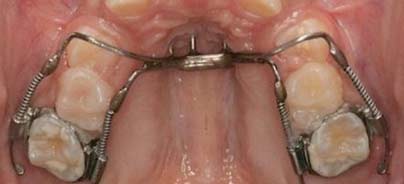

Um diese Probleme in der an­terioren Region bzw. im Reaktionsbereich zu beheben, wurden Apparaturen entwickelt, die mithilfe knochenintegrierter Implantate verankert sind.20 Diese Verfahren verhindern effektiv die Verankerungsverlus­te, jedoch benötigen sie für die Knochenintegration eine gewisse Einheilungszeit, bevor Kräfte appliziert werden können. Daneben sind zusätzliche Laborarbeiten erforderlich. Mit der Entwicklung von Miniimplantaten als temporäre Verankerungen (TADs)21–24, die zur unmittelbaren Applikation von Kräften geeignet sind, wurden Kombinationen mit bereits vorhandenen Distalisationsapparaturen möglich, die eine ossäre Verankerung bieten und dabei nachteilige Effekte an den anterioren Zähnen vermeiden.19,25–33 Ziele dieser Studien waren Design und Analyse der klinischen und radiografischen Effekte verschiedener knochengestützter Distalisationsapparaturen. Zunächst wurde eine knochengestützte Pendelapparatur (Bone Supported Pen­dulum, BSP)30,32 (Abb. 1) untersucht, die zum Schutz vor Verankerungsverlusten eingesetzt wurde. Diese Apparatur wurde gewählt, da die zahngestützte Pendelapparatur10–15 eine der am häufigsten genutzten  Distalisationsapparaturen darstellt, deren Einsatz jedoch häufig mit einer mesialen Bewegung der Prämolaren und einer la­bialen Bewegung der maxil­lären Schneidezähne einhergeht. Die BSP wurde deshalb so designt, dass sie an zwei un­spezifischen Miniimplantaten im knöchernen Gaumen mit­tels Nance-Button und einer Doppelfeder-Modifizerung16 zur Distalisierung der maxillären Molaren fixiert werden konn­te.

Es wurden fünfzehn Patienten im durchschnittlichen Alter von 13 Jahren untersucht. Zu Beginn und nach Abschluss der Zahnbewegungen wurden Studienmodelle sowie FRS und OPG zur Dokumentation der dentalen und skelettalen Veränderungen durchgeführt. Die mittlere Behandlungsdauer lag bei 7,8 Monaten. Die durchschnittliche distale Bewegung der maxillären Molaren betrug 6mm und die Inklination 11°. Die zweiten Prämolaren wurden ebenfalls um durchschnittlich 4,85 ± 1,96mm bei einer Inklination von 8,6° distalisiert. Die maxillären anterioren Zäh­ne wurden retrudiert und palatinal um 2° inkliniert. Die Mandibularebene wurde posterior um durchschnittlich 1,27° rotiert. Während der Distalisationsbewegungen31 konnten kei­ne Verluste der dentalen Verankerung festgestellt werden. Das BSP bietet einen einfachen Weg der für Distalisierungen erforderlichen  Verankerungskontrolle. Besonders vorteilhaft sind die minimalinvasive chirurgische Platzierung bzw. Entfernung und die unmittelbar mögliche Applikation von Kräften. Allerdings sind spe­zifische biomechanische Vor­bereitungen erforderlich, um nachteilige Reaktionen wie distales Tipping und distale Rotation der oberen Molaren zu vermeiden. Während der molaren Dista­lisierung wurde eine simultane Distalisierung der Prämo­laren beobachtet, wodurch sich der anteriore Engstand spontan verbesserte, was zur Verkürzung der Behandlungszeit mit festsitzenden Apparaturen führte. Die Apparatur wurde während der Retraktion der Eckzähne als Retainer belassen, wodurch der Nance Button-Haltebogen zur Verbesserung der Verankerung eingespart werden konnte.  Wenn die Miniimplantate und das BSP manuell ohne Anästhesie entfernt wurden, konnte eine leichte Irritation der palatinalen Mukosa beobachtet werden, die der bei Entfernung des Nance-Buttons vergleichbar war. Diese Irritation war auf Schwierigkeiten bei der Gewährleistung optimaler Hygiene zurückzuführen und heil­te ohne weitere Maßnahmen innerhalb von zwei bis drei Tagen ab.

Zusammenfassend lässt sich feststellen, dass das BSP sich als valide klinische Option für die Distalisierung maxillärer erster Molaren erwiesen hat, wenn eine effiziente Verankerung erwünscht ist.33 Zu seinen Vorteilen gehören die reduzier­te Behandlungszeit, die auf ei­ne Spontanverbesserung des anterioren Engstandes und die spontane distale Migration der Prämolaren zurückzuführen ist. Allerdings kann durch die Pendelbewegung eine unerwün­sch­te distale Neigung und Rota-tion der Molaren eintreten und in einigen Fällen führt die Apparatur zum posterioren Kreuzbiss, der zusätzliche kieferorthopädische Maßnahmen erforderlich macht. Zudem sollte berücksichtigt werden, dass die Apparatur nicht über einen distalen Stopp zur Verhinderung einer Überkorrektur im Fall von Non-Compliance oder vergessenen Behandlungsterminen verfügt. Dieser Fall ist im weiteren Verlauf am Beispiel eines Patienten beschrieben, der das Department of Orthodontics der CES University mit einem überkorrigierten Pendel, schweren distalen Neigungen des linken oberen Molaren und einer Impaktierung des zweiten linken oberen Molaren konsultierte (Abb. 2).